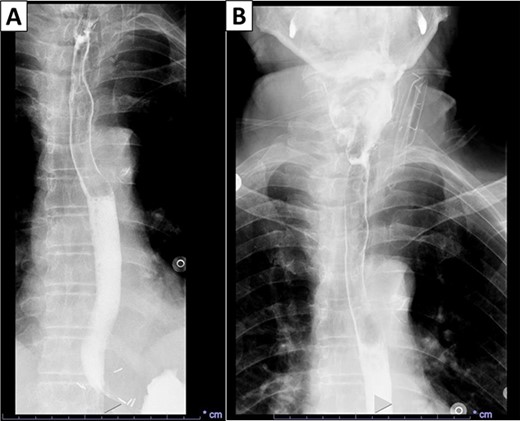

This is a case of a 74-year-old man with a history of diabetes mellitus and hyperlipidemia, who presented to our institution with chronic regurgitation, dysphagia and halitosis. The patient was initially seen in 2015 at which point he reported a 10-year history of these symptoms and was diagnosed with ZD (Fig. 1). He had frequent chocking and aspiration events and worsening symptoms in the past few months. Surgical history included cholecystectomy in 2010 and partial gastrectomy in 1989 for stomach cancer. Vital signs on admission were normal. His body mass index was 26.71 kg/m2. Physical examination and laboratory values on admission were normal. The patient never smoked and does not drink alcohol.

X-ray esophagogram performed in 2015. Esophagogram with barium suspension showed a 4 × 5 cm Zenker’s diverticulum with a 1.7 cm wide diverticular neck.